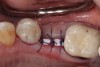

Fig 22. Bone graft was placed in the socket and a d-PTFE barrier was used to cover the graft. The bone graft material was placed beyond the alveolar housing to accommodate shrinkage of graft material and to facilitate attaining a wide alveolar ridge. The barrier was removed after 5 weeks.

Figure 22

Fig 23. Implant inserted in a regenerated ridge after 6 months healing.

Figure 23